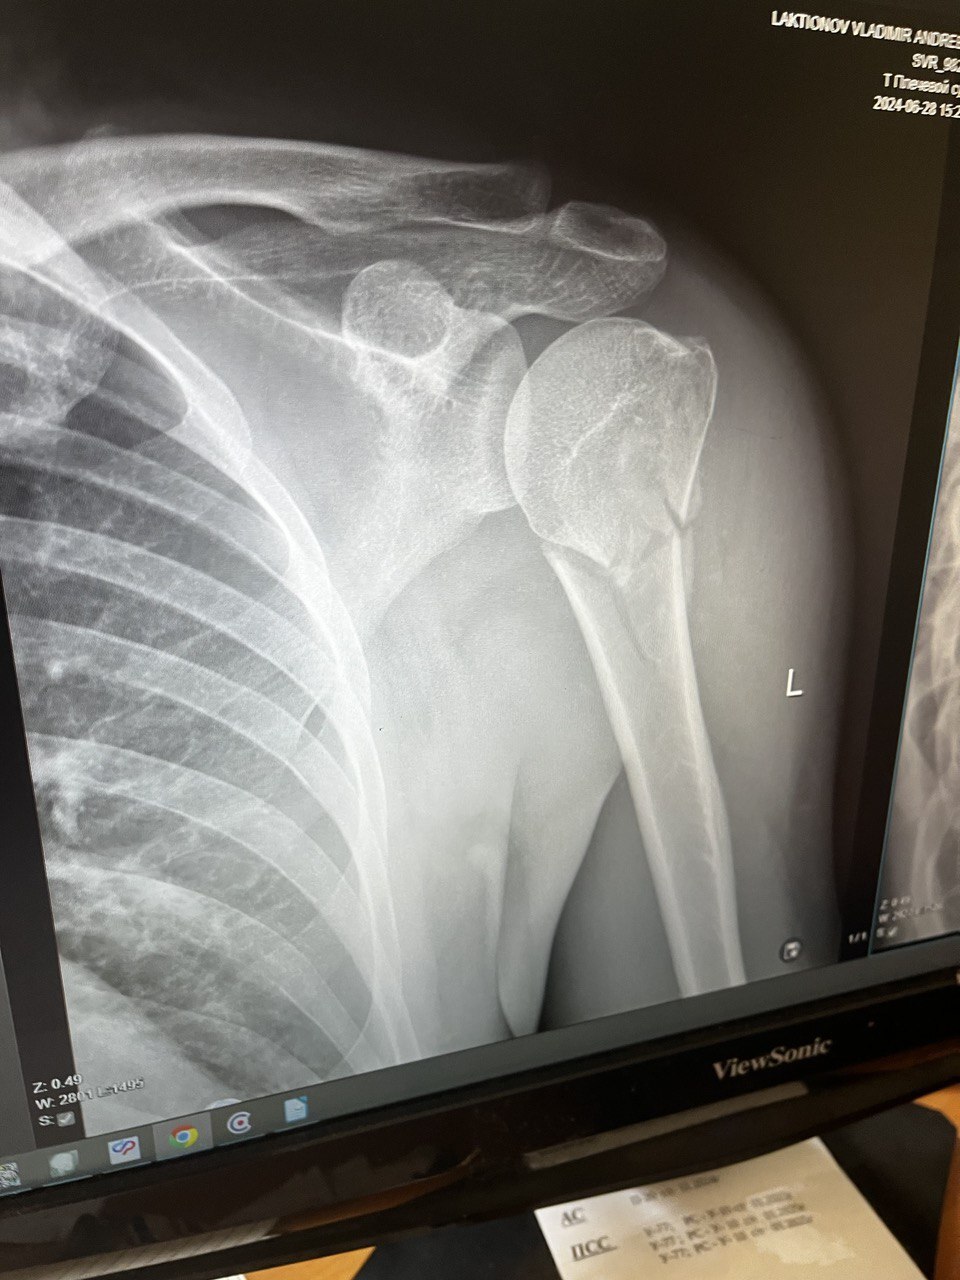

Когда дорога до больницы и очередь в травмпункте были позади я оказался в кабинете у врача который осмотрев визуально моё плечо сказал что это мало вероятно что это ключица и отправил на рентген в соседнем кабинете. Вернувшись к врачу в кабинет я увидел что он уже рассматривает мой снимок на своём компьютере. Врач сказал что хорошо постарался и потребуется операция по установке пластины и начал готовить документы для госпитализации и что бы я не скучал медсестра сводила в процедурный кабинет где поставила укол обезболивающего(до этого я пил только анальгин который не особо помогал при такой боле).

Результат покатушки: Перелом верхнего конца плечевой кости закрытый.